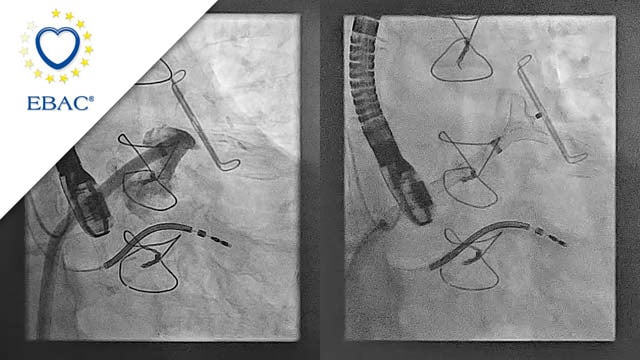

Degenerated bioprosthesis and Bentall surgery: how to track and position the valve with an angulated ascending aorta conduit?

06 Feb 2025

Complex procedures, such as TAVI in patients with a degenerated bioprosthesis and a Bentall surgery history, demand meticulous planning. This case highlights the importance of computed tomography imaging to minimize procedural risks and explores the snare strategy for navigating anatomical constraints. Learn how this approach, adaptable to...